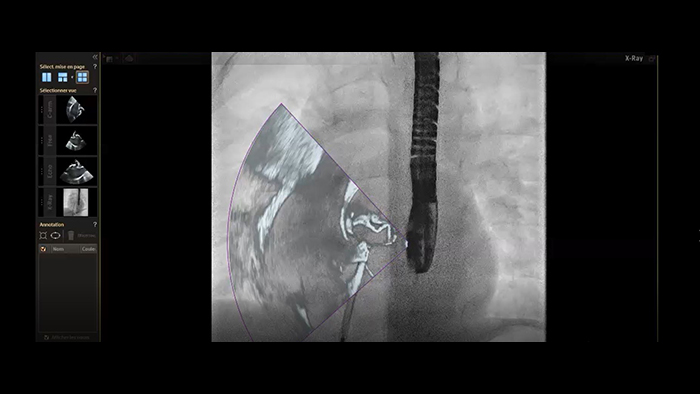

Zamknięcie ASD — łączenie obrazów w czasie rzeczywistym w systemie EchoNavigator